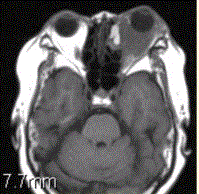

患者女,64岁,左眼突出5年余。查体左眼球前突6mm,眼球运动自如,眼底无异常,下睑扪及边界不清、质软的肿块,视力正常,MR表现如下图。临床拟...

问题 患者女,64岁,左眼突出5年余。查体左眼球前突6mm,眼球运动自如,眼底无异常,下睑扪及边界不清、质软的肿块,视力正常,MR表现如下图。 临床拟诊为

选项 A.眶内炎性假瘤 B.眼型Grave病 C.黑色素瘤 D.转移瘤 E.眼眶海绵状血管瘤 F.弥漫型淋巴管瘤

答案 A